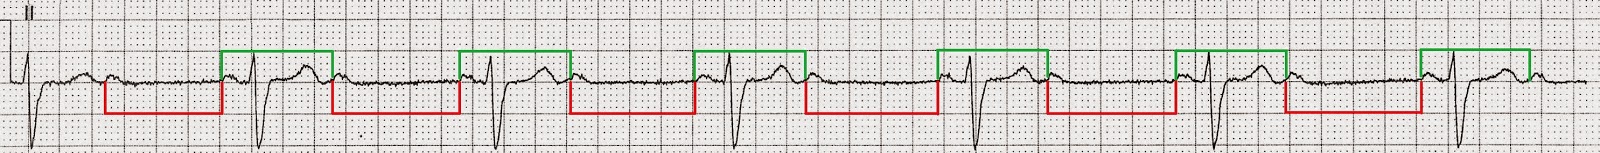

- Short P-P (Green) followed by long P-P (Red) - see image below

- The shorter P-P interval occurs when a ventricular (QRS) complex occurs between the P waves whilst the longer P-P interval occurs when there is no ventricular (QRS) complex between the P waves

- This phenomenon is known as Ventriculophasic Arrhythmia

- 2:1 AV Block with ventricular (QRS) complexes only occurring after every second P wave